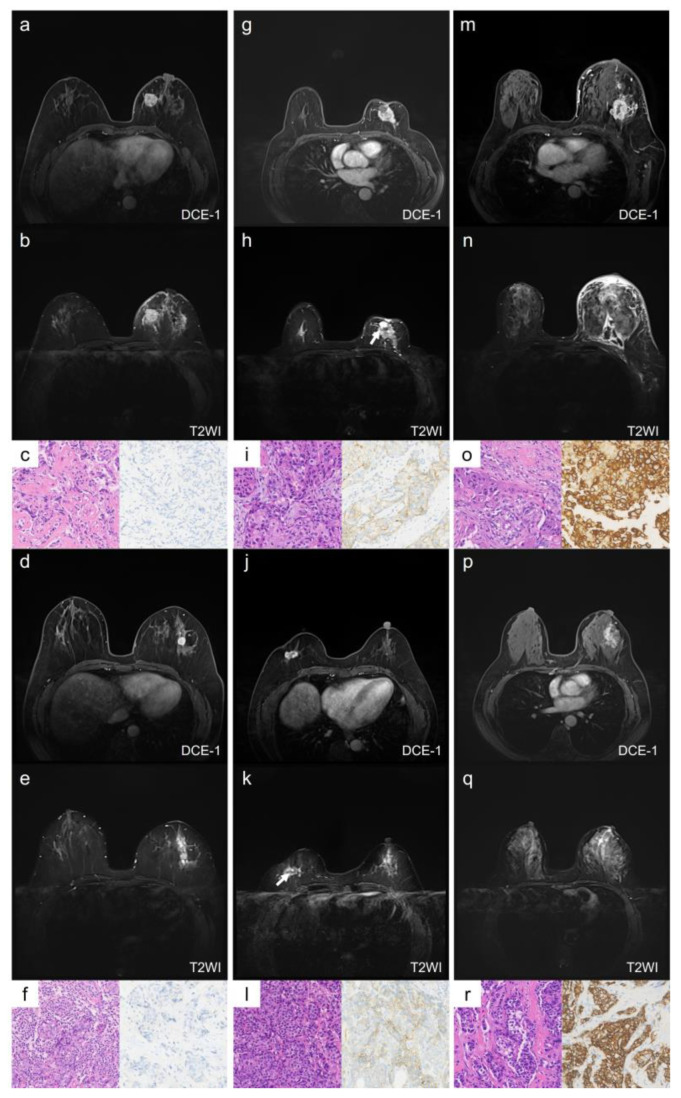

Methods: Pre-treatment breast MRI images from 232 patients with pathologically confirmed breast cancer were retrospectively analyzed. Both clinicopathologic and MRI features were recorded. Qualitative MRI features included Breast Imaging Reporting and Data System (BI-RADS) descriptors from dynamic contrast-enhanced MRI (DCE-MRI), as well as intratumoral T2 hyperintensity and peritumoral edema observed in T2-weighted imaging (T2WI). Quantitative features were derived from diffusion kurtosis imaging (DKI) using multiple b-values and included statistics such as mean, median, 5th and 95th percentiles, skewness, kurtosis, and entropy from apparent diffusion coefficient (ADC), Dapp, and Kapp histograms. Differences in clinicopathologic, qualitative, and quantitative MRI features were compared across groups, with multivariable logistic regression used to identify significant independent predictors of HER2-low breast cancer. The discriminative power of MRI features was assessed using receiver operating characteristic (ROC) curves.

Results: HER2 status was categorized as HER2-zero (n = 60), HER2-low (n = 91), and HER2-overexpressed (n = 81). Clinically, estrogen receptor (ER), progesterone receptor (PR), hormone receptor (HR), and Ki-67 levels significantly differed between the HER2-low group and others (all p < 0.001). In MRI analyses, intratumoral T2 hyperintensity was more prevalent in HER2-low cases (p = 0.009, p = 0.008). Mass lesions were more common in the HER2-zero group than in the HER2-low group (p = 0.038), and mass shape (p < 0.001) and margin (p < 0.001) significantly varied between the HER2 groups, with mass shape emerging as an independent predictive factor (HER2-low vs. HER2-zero: p = 0.010, HER2-low vs. HER2-over: p = 0.012). Qualitative MRI features demonstrated an area under the curve (AUC) of 0.763 (95% confidence interval [CI]: 0.667-0.859) for distinguishing HER2-low from HER2-zero status. Quantitative features showed distinct differences between HER2-low and HER2-overexpression groups, particularly in non-mass enhancement (NME) lesions. Combined variables achieved the highest predictive accuracy for HER2-low status, with an AUC of 0.802 (95% CI: 0.701-0.903).